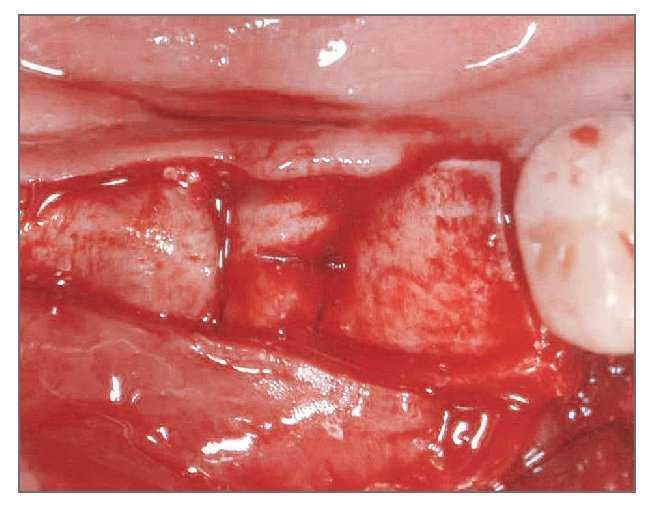

El paciente se enjuagó con colutorio de clorhexidina al 0,12% (Hexamedine, Bukwang) durante 2 min antes de la operación. Después de aplicar anestesia local con lidocaína al 2% y epinefrina 1:100.000, se levantó un colgajo de espesor total, poniendo de manifiesto el defecto óseo del alveolo vestibular. La dehiscencia vestibular era de 2,0 a 6,0 mm apicoronalmente. Se colocaron tres implantes de 3,8 x 12,0 mm (Implantium, Dentium) en el área molar de la mandíbula derecha con un torque de inserción de 40 Ncm (fig. 2). El defecto remanente y los vacios marginales se injertaron con hueso bovino deproteinizado (Bio-Oss, Geistlich Pharm) (fig. 3). Se empleó MDA para cubrir completamente el injerto óseo y asegurarlo bajo los colgajos vestibular y lingual (fig. 4). A continuación, se reposicionó el colgajo y se cerró la herida con suturas simples (Ethicon, Johnson & Johnson Medical).

Figura 3 (derecha). El área del defecto vestibular se rellenó con hueso bovino deproteinizado.

Figura 4 (izquierda). Se modeló el MDA para cubrir completamente el defecto y el injerto óseo.